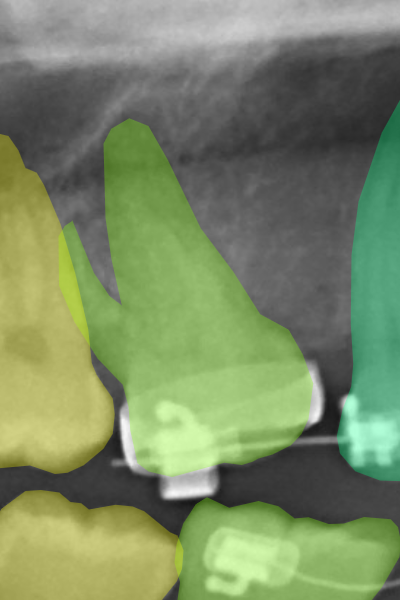

Figure 3 displays corresponding label samples of the aforementioned criteria. We followed the same criteria to label 400 additional images (40 per radiograph category). These images compounded our test set for assessing the neural networks trained at each HITL iteration.

Refer to caption

(a) Implants.

(b) Protheses.

(c) Molar roots.

(d) Restorations.

(e) Appliances.

Figure 3: Label samples of the employed criteria for annotating implants, prostheses, molar roots, restorations, and dental appliances. In general, the labels should be more refined on sharp and well-focused images, while in blurry images, the annotators should rely more on the tooth anatomical structures.